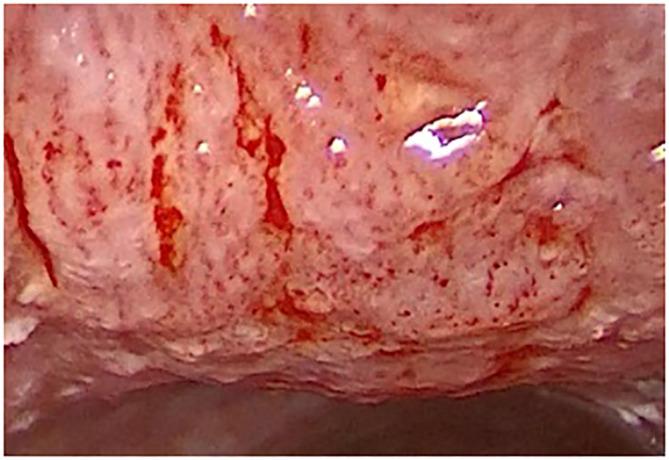

Scattered, small, dot-like intraepithelial papillary capillary loops (IPCLs) represent type IV epithelial vascularization according to "Ni classification" and are considered to be nonmalignant. According to the European Laryngological Society classification, these loops are malignant vascular changes. This contradiction has high clinical importance; therefore, clarification of the clinical significance of type IV vascularization according to the Ni classification is needed.

A total of 674 lesions (434 patients) were investigated using flexible NBI endoscopy and IMAGE1 S endoscopy. Type IV vascularization was recognized in 293/674 (43.5%) lesions. Among these 293 lesions, 178 (60.7%) were benign (chronic laryngitis, hyperplasia, hyperkeratosis, polyps, cysts, granulomas, Reinkeho oedema and recurrent respiratory papillomatosis); 9 (3.1%) were squamous cell carcinoma; 61 (20.8%) were mildly dysplastic, 29 (9.9%) were moderately dysplastic, 14 (4.8%) were severe dysplastic and 2 (0.7%) were carcinoma in situ. The ability to recognize histologically benign lesions in group of nonmalignant vascular pattern according to Ni (vascularization type I-IV) and distinguish them from precancers and malignancies was with accuracy 75.5%, sensitivity 54.4%, specificity 94.4%, positive predictive value 89.6% and negative predictive value 69.9%.

Laryngeal lesions with type IV vascularization as defined by Ni present various histological findings, including precancerous and malignant lesions. Patients with type IV vascularization must be followed carefully and, in case of progression mucosal lesion microlaryngoscopy and excision are indicated.